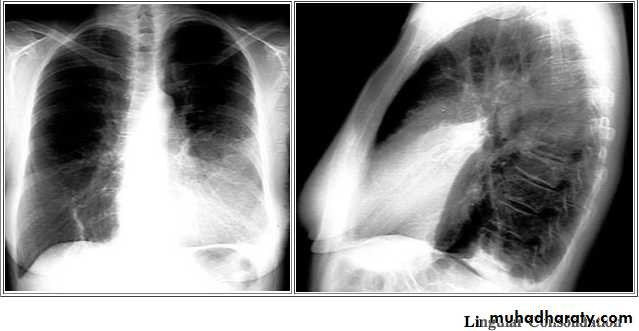

Standard views are the PA & Lateral

PA ( frontal ) VIEW LT. LATERAL VIEW

Lateral view

IndicationsAnterior mediastinal mass

Encysted pleural fluids

Posterior basal consolidation